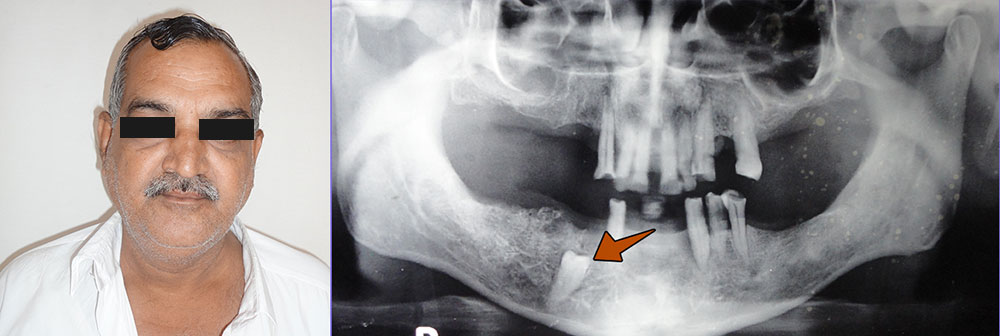

[caption id="attachment_1338" align="alignnone" width="1000"]

Impacted-premolar-Balram[/caption]

We happened to have treated a rare of the rarest impacted premolar case at

Jerush dental and facial corrective centre. Mr. Balaram (name changed), aged 59 with an impacted premolar approached us for treatment. Throbbing and pulsating inflammation every now and then was his reason to visit us. An x-ray clearly showed the impacted condition of his tooth. All precautionary measures meant for the extraction of an elderly patient were followed before surgically removing the impacted tooth. Balram smiled at us with gratitude.